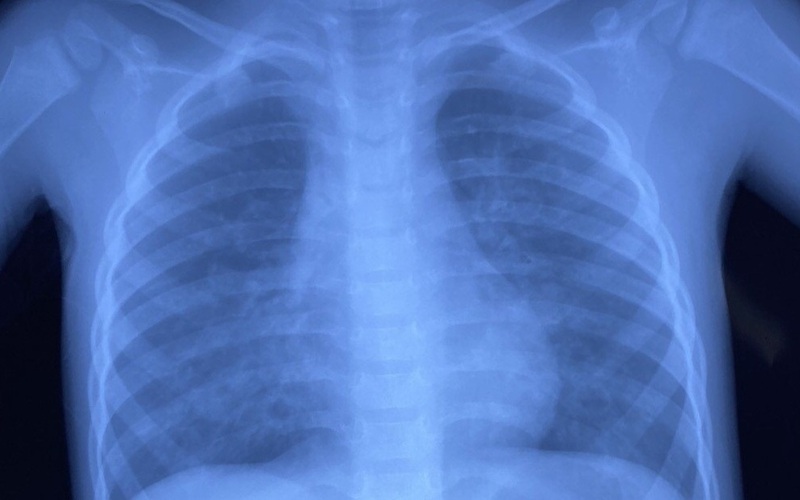

Khi vào viện, các bác sĩ nhanh chóng xử trí cấp cứu ban đầu, sau đó kiểm tra các cận lâm sàng cần thiết. Kết quả nội soi họng cho thấy ít máu đọng thành sau họng, theo dõi viêm phổi hít.